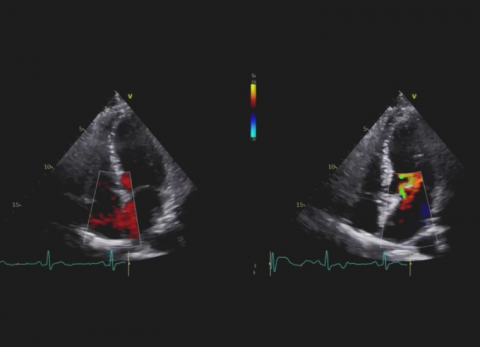

Wideo Echokardiografia. Przypadek 8

prof. dr hab. n. med. Piotr LipiecPacjentka dusznością wysiłkową; w wywiadzie leczenie operacyjne z powodu raka pęcherza moczowego.